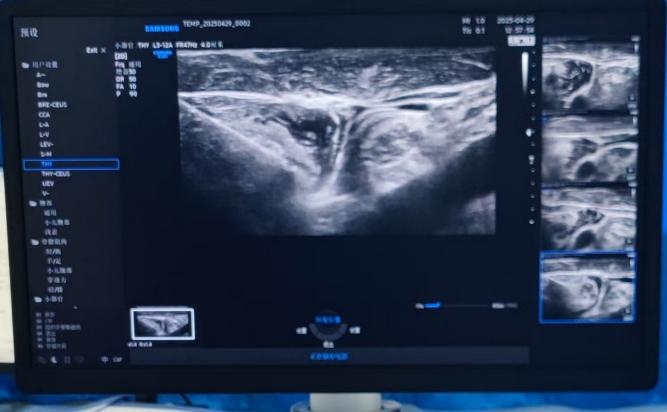

团队成员围绕李女士的病情,展开了多轮深入探讨,从治疗方案的可行性,到操作过程中的每一个细节,都反复斟酌。经过充分的讨论与论证,最终敲定以「超声引导下冷循环微波消融术」作为治疗方案,力求为患者带来最佳的治疗效果 。

手术当天,主导医师在超声设备的引导下,对病灶定位确定治疗点;然后使用微波针「以针代刀」,通过针尖大小的创口,利用微波的热效应和冷循环系统的协同作用,精准、有效地消融病变组织,同时降低对周围正常组织的不良影响。